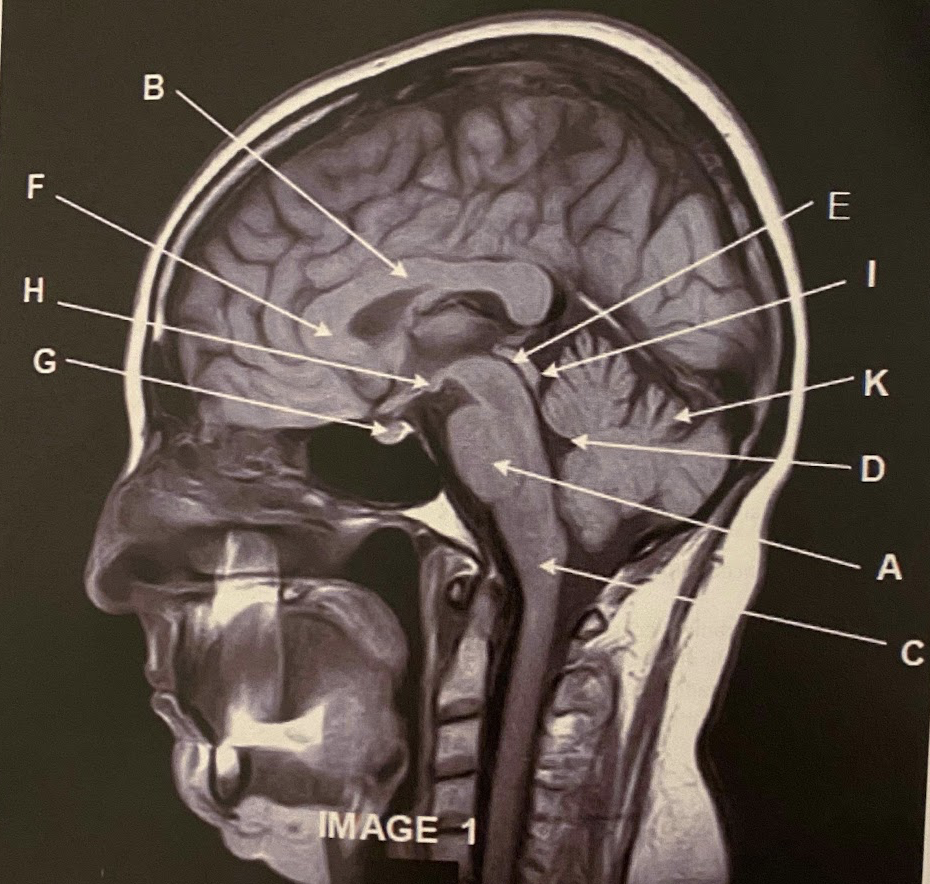

1

Q

The sagittal scan, demonstrates typical hyper intense tendril-like projections in the corpus callous characteristically seen in patients with what disease?

A) Tuberous Sclerosis

B) Multiple Calcified Nodules

C) Multiple Sclerosis

A

What anatomy is letter A pointing to?

Pons

3

What anatomy is letter B pointing to?

Corpus Callosum

How well did you know this?

Not at all

2

4

5

Perfectly

What anatomy is letter C pointing to?

Medulla Oblongata

What anatomy is letter D pointing to?

Fourth ventricle

6

What anatomy is letter E pointing to?

Aqueduct of Sylvius

7

What anatomy is letter F pointing to?

Genu of the corpus callous

8

What anatomy is letter G pointing to?

Pituitary

9

What anatomy is letter H pointing to?

Mammillary Bodies

10

What anatomy is letter I pointing to?

Quadrigeminal plate

11

This image is non-contrasted. It was acquired using a _______ sequence

A) Proton Density

B) T1

C) FLAIR

D) GRE